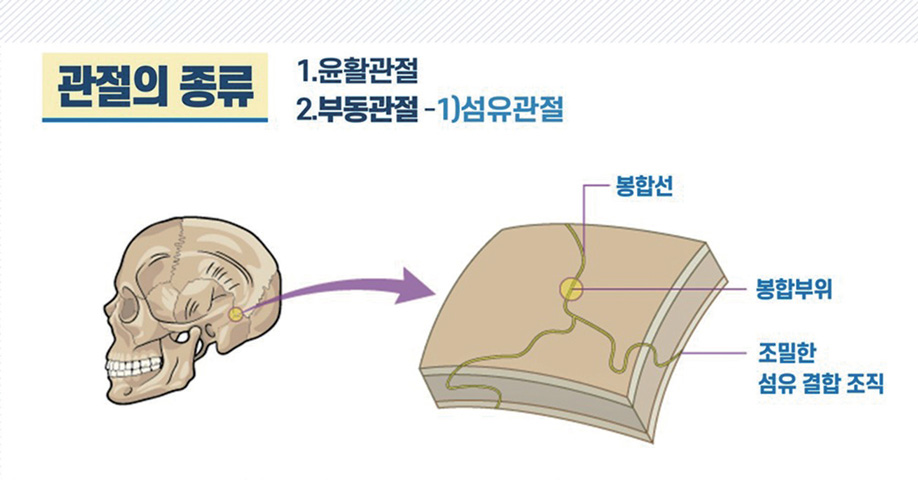

관절의 종류를 보면 크게, 움직일 수 없는 부동관절不動關節(Synarthrosis)과 움직일 수 있는 가동관절可動關節(Diarthrosis)로 나눠집니다. 움직일 수 없는 부동관절은 다시 두 가지로 나눠 볼 수 있는데요. 섬유관절纖維關節(Fibrous joint)과 연골관절軟骨關節(Cartilaginous joint)입니다.

- 부동관절① 섬유관절